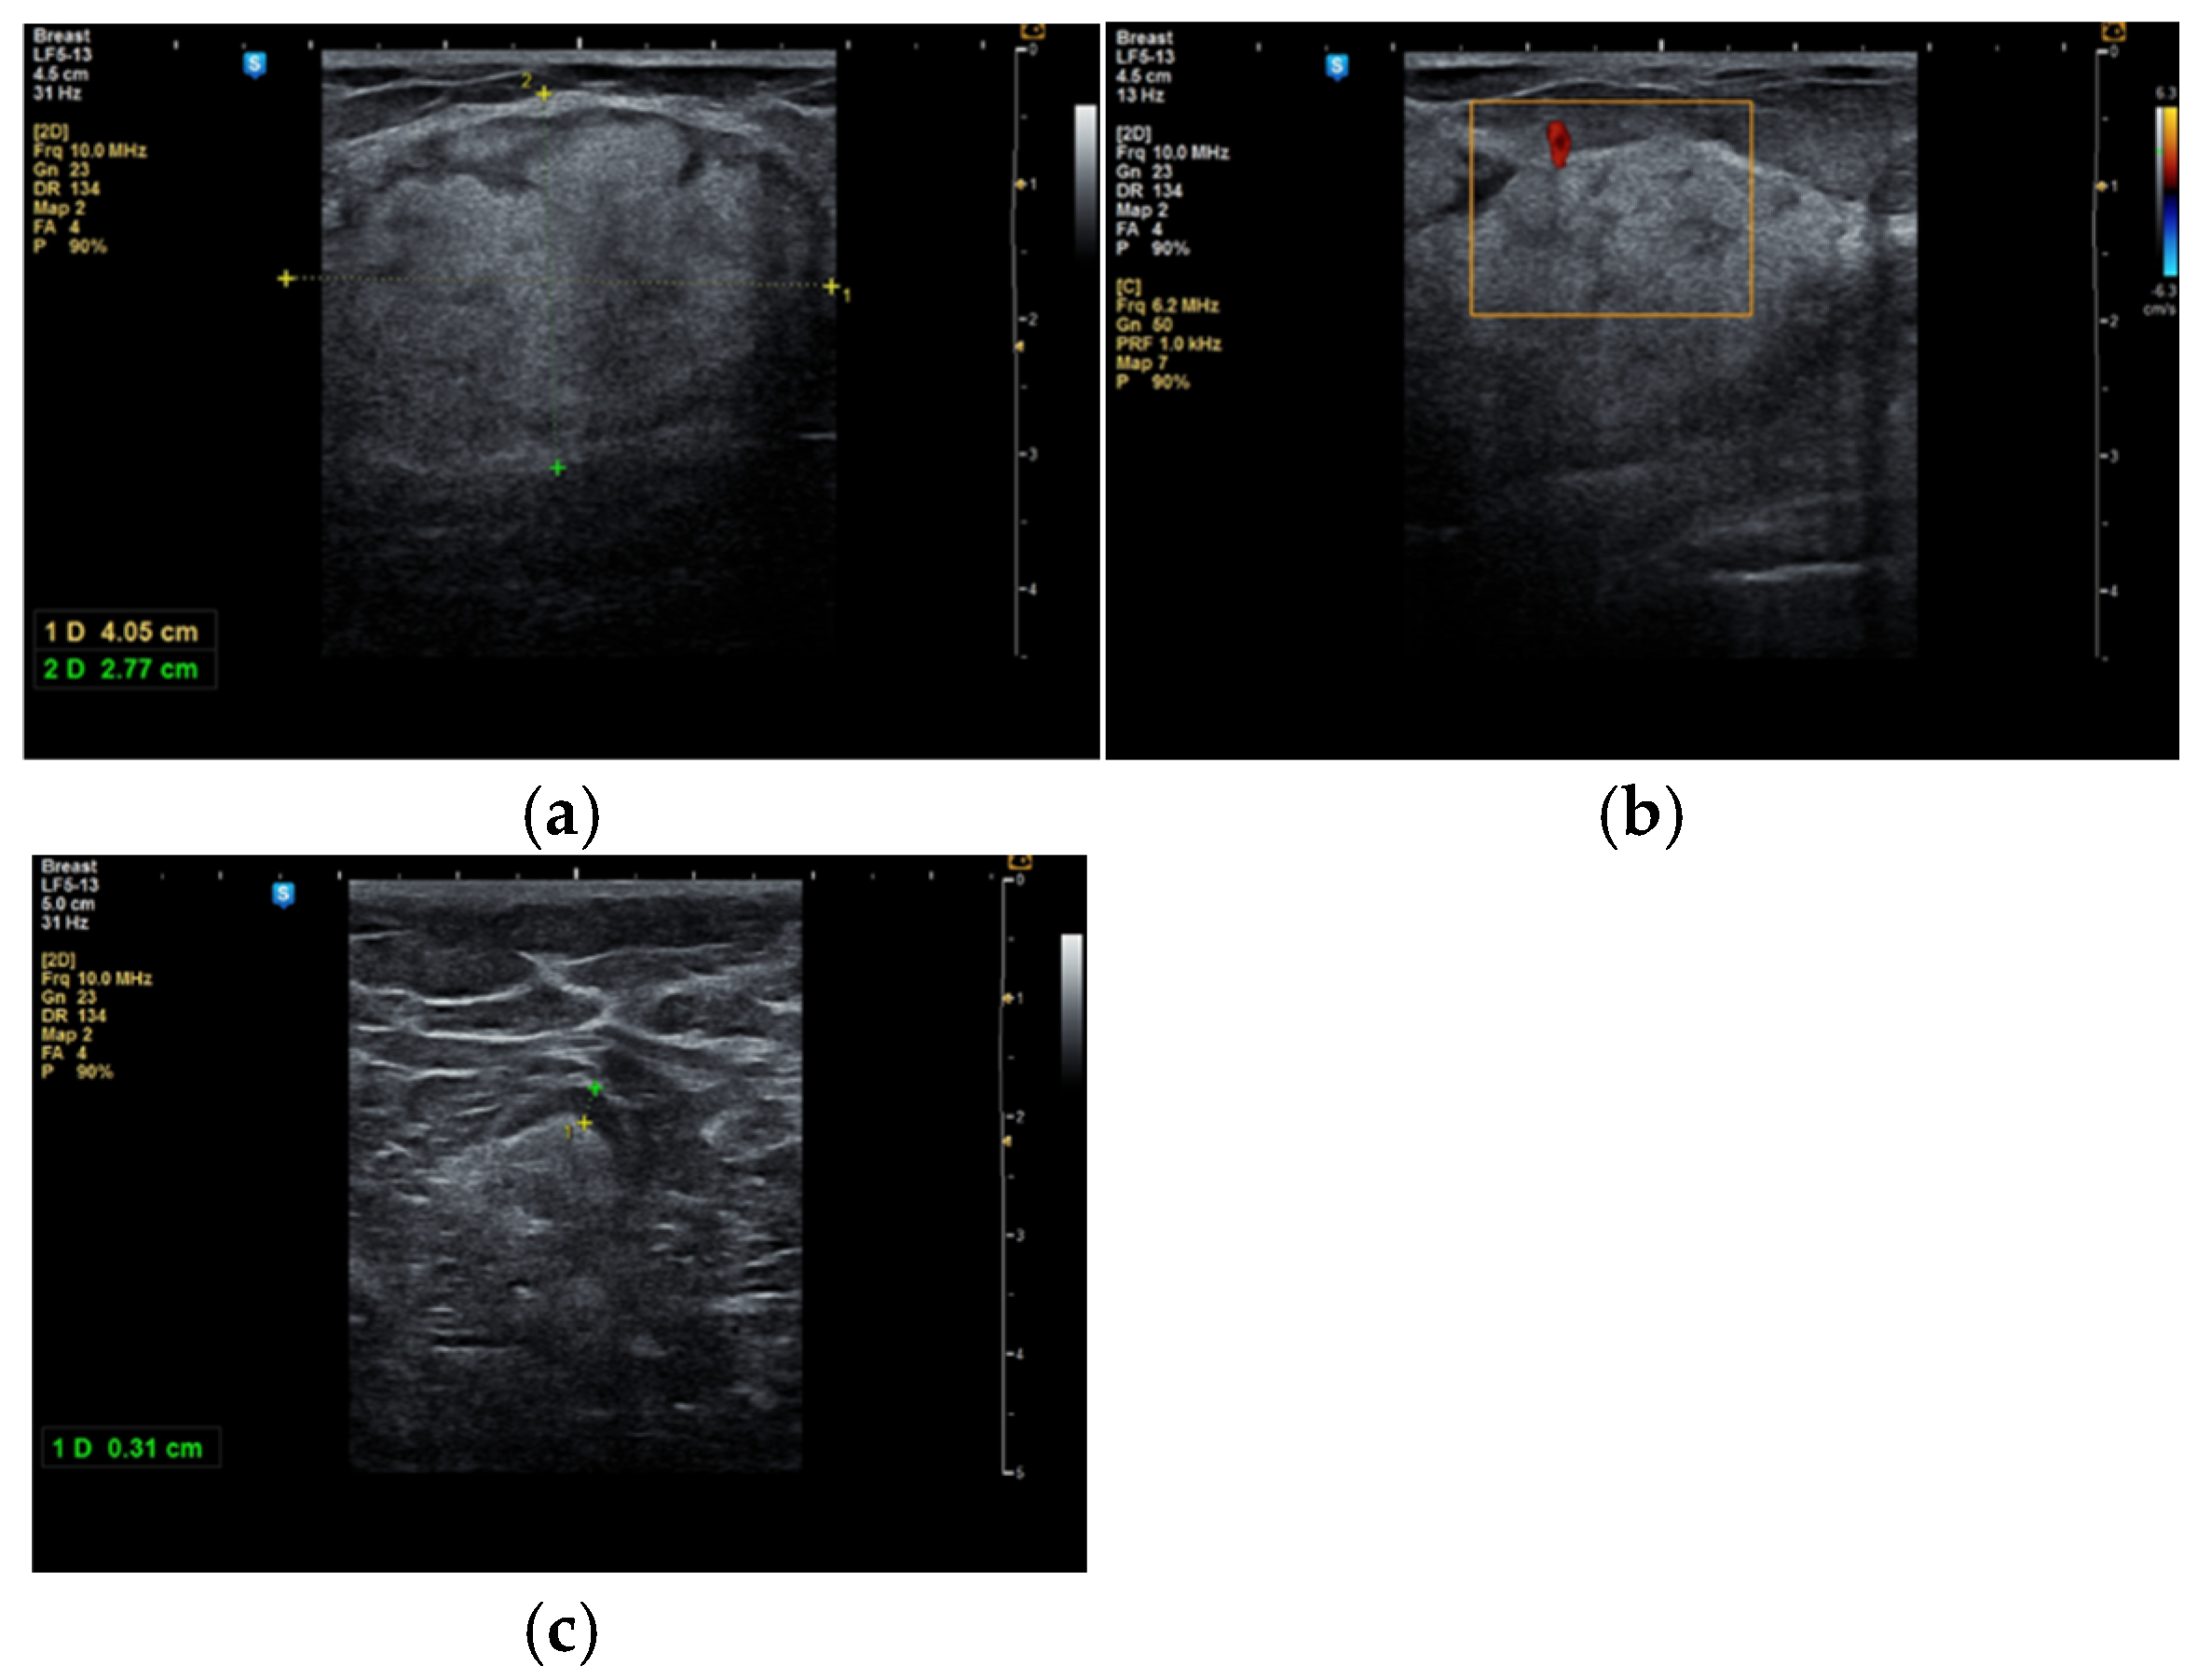

Although the literature identifies mammography as the primary diagnostic method for breast hamartomas, in our study, the diagnosis was established via ultrasound examination. This preference is due to the younger age of many patients, with only three being over 50 years old. On ultrasound, hamartomas typically appear as oval, well-circumscribed masses with heterogeneous hypoechoic or isoechoic echostructures and reduced or absent vascularity (Figure 1 and Figure 2). In our study, the concordance between ultrasound and histological size was 84.61%. Preoperative ultrasound diagnosis of hamartoma was established in only five patients, representing 38.46% of the cases.

In some cases, the diagnosis was initially suspected to be a malignant tumor (Figure 3a–c).

Figure 3. A 53-year-old woman with a tumor in the right upper outer mammary quadrant (a) with predominant hyperechoic structure; (b) with a peripheral vessel; (c) with benign axillary adenopathy.